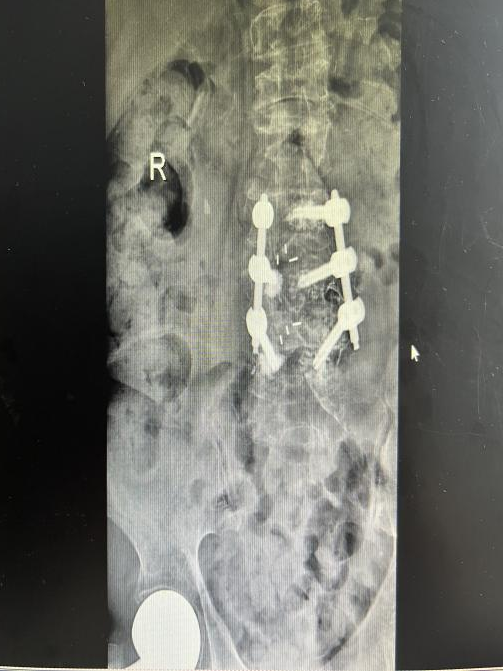

4月23日,贵州航天医院第58次晨读会由我院骨科副主任医师张艳金作学术交流,他以“加速康复指导下的快速手术”为题,详细讲解了老年股骨粗隆间骨折与儿童四肢骨折的临床诊疗难点,结合加速康复外科(ERAS)核心理念,重点阐述了ERAS理念在两大人群中的创新实践,实现患者入院后6至24小时内即可接受手术治疗。针对老年髋部骨折患者,提出通过多学科协作(MDT)与微创手术优化围术期管理,在确保安全前提下缩短术前等待时间,实施精准化麻醉及术后康复方案,可有效降低并发症发生率、改善患者生活质量和预后效果。在儿童骨折领域,强调微创术式与心理干预并行的双轨策略,既减少手术创伤对骨骼发育的影响,同时关注患儿心理疏导,实现生理功能与心理健康同步康复。并通过典型案例的影像学资料与随访数据,直观展示了ERAS理念指导下骨科治疗模式的创新成果。 贵州航天医院骨科 专家简介 赵学平 中共党员,骨科党支部书记、主任,主任医师 临床擅长:从事骨科临床工作30余年,对骨科常见疾病的诊治具有丰富的临床经验。 世界中医药联合会脊柱康复专业委员会常务理事,中华中医药学会整脊分会常务委员,中国中西医结合学会骨伤科分会肢体矫形功能重建与康复专家委员会常务委员,中国研究性医院学会骨科创新与转换专业委员会关节外科学组保髋工作委员会常委,中国康复技术转化及发展促进会骨外科与康复技术转化专业委员会常务委员,泛珠三角区域运动医学联盟(PPRD-SMA)理事会常务理事,中国研究型医院学会运动医学专业委员会委员,贵州省中医药学会整脊分会副主任委员,贵州省中西医结合学会银质针专业委员会副主任委员,贵州省康复医学会骨与关节专业委员会常务委员,贵州省人民医院骨科专科联盟常务理事,贵州省康复医学会骨内科专业委员会常务委员,中华医学会贵州省骨科学会委员,贵州省康复医学会脊柱脊髓专业委员会常务委员,贵州省运动医学分会委员,贵州省康复医学会骨与软组织肿瘤专业委员会委员,遵义市医学会创伤分会副主任委员,贵州省康复医学会骨内科专业委员会遵义地区分会常务委员,遵义市医疗事故鉴定、伤残鉴定、工伤鉴定、司法鉴定专家。 长期从事骨科临床研究及教学工作,在国家级、省部级杂志发表论文20余篇,SCI论文2篇,参与主编骨科专著2部,主持省部级科研项目2项,参与指导省部级、市级科研项目6项。 陈明勇 骨科副主任,副主任医师 临床擅长:从事创伤骨科工作约20年,对骨缺损、骨不连、骨肿瘤、肢体畸形等的肢体矫形重建及功能重建,慢性化脓性骨髓炎的根治治疗、糖尿病足的保肢治疗、快速康复理念(ERAS)下的老年骨折的诊治,四肢复杂骨折的诊治,四肢骨折等微创手术治疗具有丰富的临床经验。 2004年毕业于遵义医学院临床专业,曾在中国人民解放军总医院、广西医科大学第一附属医院、上海第六人民医院骨科进修。中国中西医结合学会骨伤科专业委员会横向骨搬移治疗糖尿病足及微血管网再生学组首届委员,遵义市医学会创伤分会常务委员。 瞿 辉 中共党员,骨科副主任医师 临床擅长:对骨科的常见病、关节外科、脊柱外科及运动医学疾病的诊治具有丰富的临床经验,熟练掌握骨科手术操作技术。 毕业于遵义医学院临床医学系,2005年前往广州中山大学第一附院骨显微医学部进修学习,2011年前往成都华西医院进修学习,并多次在省内外学习骨科相关知识,是中华医学会骨科分会会员。 赵兴东 骨科主任医师 临床擅长:擅长骨科的常见病及各种创伤、四肢骨折创伤修复、骨感染、手足疾病的诊治和手足体表畸形的矫形整复,熟练掌握骨科四肢骨病及创伤的手术操作技术,尤其在四肢关节复杂性损伤、手足外伤、组织缺损创面、难治创面的皮瓣修复方面及平足、高弓足矫形方面及四肢慢性疼痛诊治、康复方面具有丰富的临床经验。 硕士研究生,毕业于遵义医学院临床外科系,2015年前往山东省立医院手足外科进修学习;遵义市医学分会创伤分会第一、二届委员,遵义市手外科医学会第二委届员会常务委员;在省级及省级以上期刊发表文章9篇,参编著作2部,参与主持并完成市级课题1项,参与市级课题2项、省级课题1项。 张艳金 中共党员,骨科副主任医师 临床擅长:从事骨外科工作16年,对复合伤、多发伤的救治、四肢骨干骨折、关节周围骨折、骨肿瘤、骨髓炎等诊治具有丰富的临床经验。 中共党员,硕士研究生,2006年本科毕业于山西医科大学第二临床医学院,2011年研究生毕业于北京军区总医院;在“老年COPD患者合并髋部骨折的诊治”国际合作课题组研究两年,在老年髋部骨折的诊治方面具有丰富的经验,并发表论文6篇;主持遵义市级课题1项,承担遵义医科大学的临床教学工作,获得遵义医科大学优秀带教老师荣誉。编撰有《骨科疾病诊疗精粹》一书,开展2项新技术,编撰地方规范《务川自治县创伤骨科常见疾病诊疗规范》一书。 张俊凯 骨科副主任医师 临床擅长:从事骨科临床工作28年,对创伤骨折、骨感染、骨缺损、骨不连等外科诊治,四肢骨折的微创手术治疗,四肢复杂骨折(如关节内粉碎性骨折、多发骨折等)的损伤控制及手术治疗等具有丰富的临床经验。 1995年毕业于遵义医学院临床专业,2009年前往复旦大学附属医院骨科进修1年。 卢懿明 中共党员,骨科副主任医师 临床擅长:从事骨科工作18年,对创伤骨折、四肢骨折的微创手术治疗、四肢复杂骨折(如关节内粉碎性骨折、多发骨折等)的损伤控制及手术治疗,尤其是髋部骨折的PFNA等微创技术,踝关节骨折、膝关节周围骨折的Mipo微创技术等具有丰富的临床经验,开展了4项新技术,发明6项新型专利技术。 2005年毕业于遵义医学院临床专业,2017年,前往南方医科大学第三附属医院骨科进修半年,回院后运用Mipo技术对骨干骨折及干骺端骨折的治疗技术,同时积极开展骨盆骨折、髋臼骨折腹直肌外侧切口的应用;发表了多篇专业论文,经常参与省内外学术交流会授课,获得医院荣誉称号多个。 邬夏荣 骨科副主任医师 临床擅长:从事骨科工作16年,对四肢复杂骨折、骨肿瘤的诊治,尤其是足踝创伤、慢性踝关节损伤、平足症等诊疗具有丰富的临床经验。 2006年毕业于遵义医科大学临床医学专业,曾在陆军军医大学西南医院进修学习,发表多篇骨科学术论文。 余德怀 中共党员,骨科副主任医师 临床擅长:从事骨科工作10余年,对运动医学、骨关节、脊柱外科常见病、多发病的诊治具有丰富的临床经验。 硕士研究生,2011年毕业于遵义医学院临床医学专业,曾前往遵义医科大学附属医院运动医学专业进修学习;是贵州省医学会运动医学分会青年委员,西部关节镜联盟委员;发表多篇骨科学术论文。 冯 乾 骨科副主任医师 临床擅长:从事骨科工作近20年,熟练掌握骨科多发病及常见病的诊治,尤其对脊柱退变性疾病的诊断及治疗具有丰富的临床经验,主要研究脊柱微创相关治疗方式,能熟练开展椎间孔镜及UBE。 曾前往北京大学第三医院进修学习疼痛及椎间孔镜、首都医科大学友谊医院专业进修脊柱内镜;是贵州省康复医学会第三届脊柱脊髓专业委员会委员;发明专利3项、发表脊柱外科专业论文多篇。 赵小锋 中共党员,骨科副主任医师 临床擅长:从事骨科临床工作11年,对骨科常见病、多发病诊疗有较为丰富的临床经验,擅长脊柱相关疾病诊断及治疗,尤其是颈、腰、腿疼痛疾病诊断及治疗,擅长胸腰椎骨折微创经皮穿刺内固定术、经皮穿刺椎体成形术、经皮穿刺脊柱内镜下腰椎间盘摘除术、单纯开创腰椎间盘摘除术、腰椎滑脱复位椎间植骨椎融合内固定术、腰椎管狭窄减压融合内固定术及人工髋、膝关节置换术等。 2012年毕业于遵义医学院外科学专业硕士研究生,2019年参加“遵义市115医学人才精英计划”于上海交通大学第一附属医院培训学习,2023年于北京大学第三人民医院脊柱外科进修学习,曾获得遵义市优秀医师荣誉称号。 遵义市手外科第一届委员,遵义市医学会创伤分会第一届委员,遵义市医学会创伤分会第二届委员,贵州省康复医学会第三届脊柱脊髓专业会委员,遵义市医学会烧伤与整形外科学分会委员,发表论文5篇,其中国家级核心期刊1篇,SCI论文1篇,主持市级课题1项并结题,参与市级课题2项。 贵州航天医院骨科 简介 基本情况 贵州航天医院骨科组建于20世纪60年代,前身是以创伤和断肢(断指)再植闻名于世的上海市第六人民医院骨科,中国断肢(断指)再植的奠基者、中科院院士陈仲伟等著名专家、学者多次莅临科室指导医疗、教学,是贵州省最早拥有专业骨科技术科室之一,在70年代开展了贵州省首例断肢(断指)再植手术。组建50余年来,诊治患者已逾百万,挽救了无数的伤病员,成为了保障遵义地区人民群众健康的重要支撑。 经过几代人的不懈努力,今天的骨科,已由创伤骨科发展至骨病、骨肿瘤、骨结核等领域,现有脊柱外科、关节外科、四肢创伤、手足外科四个亚专科,成为了集医疗、教学、科研于一体的综合学科,是贵州省临床重点专科、遵义市临床重点专科、遵义市骨科临床医学中心、遵义市基层骨科专科联盟理事长单位。 科室目前开放床位110张,共有医护人员50余人,副高级以上专家18人,硕士研究生15人。拥有一流骨科医疗设备多台,每年不定期选派优秀技术骨干到全国各大知名医学院校进修、学习、参观、交流,并邀请国内、国外知名专家教授来院进行交流、指导,通过不断引进国内外先进的诊疗技术,科室医疗技术水平稳步提升,为广大人民群众提供了优质的医疗服务。 专科特色 骨一科 (一)骨缺损、骨不连的肢体与功能重建 胫骨横向骨搬移技术治疗糖尿病足: (二)慢性骨髓炎的根治治疗 (三)肢体缺血性疾病如糖尿病足、脉管炎的保肢治疗 (四)皮瓣修复 (五)复杂创伤的治疗 (六)老年髋部骨折及小儿骨折快速手术 老年髋部骨折: 骨二科 (一)胸腰椎骨折微创经皮椎弓根螺钉固定术 (二)老年性骨质疏松性患者腰椎滑脱脊柱内固定术(骨水泥螺钉) (三)V形双通道脊柱内镜技术(VBE)腰椎融合术治疗腰椎退行性疾病 (四)老年性骨质疏松性骨折(PVP/PKP)术 (五)人工髋关节置换术 (六)双侧股骨头坏死人工全髋关节置换 (七)右侧全髋置换术后假体周围骨折翻修 (八)人工膝关节置换术 (九)人工膝关节假体松动翻修 (十)关节镜技术 传统手术切口 关节镜技术切口 诊疗范围 骨一科 1.四肢创伤、矫形。 2.手、足踝外科。 骨二科 end